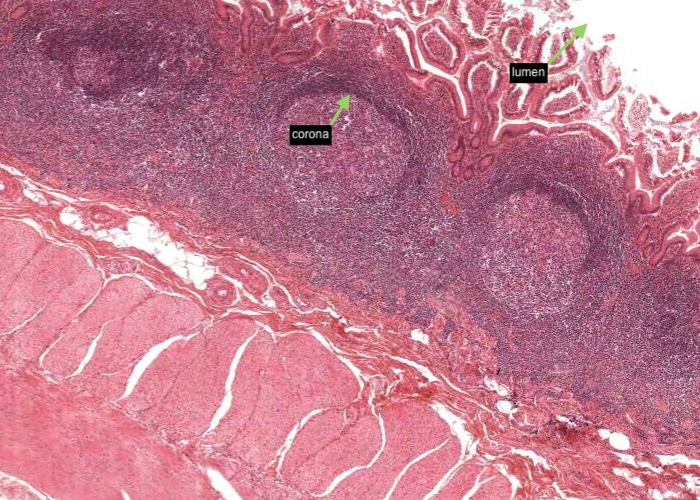

The appendix represents a small blind outpocketing of the large intestine. The mucosal and submucosal layers have been entirely converted into a mass of lymphoid tissue. Note the similarity in structure between the appendix and the tonsil. Both contain enormous depots of lymphoid tissue separated from a dirty, stagnant space or lumen by an epithelium infiltrated with lymphocytes. Tonsils alert the immune system to the resident bacteria in the throat. The appendix stimulates immunity to the range of bacteria that colonize the other end of the GI tract.

The mucosal layer and submucosal layer have been entirely converted into a mass of lymphoid tissue. Only the muscularis externa is a clearly recognisable typical layer of the gut wall.

Enormous depots of lymphoid tissue within the mucosa and submucosa are separated from a stagnant lumen by an epithelium infiltrated with lymphocytes.